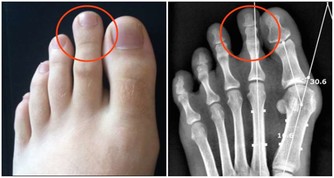

8.強健骨骼:走路能夠避免骨質疏鬆,對於年長者來說特別重要。對於年長女性而言,每天走路30分鐘就能夠減少30%髖部骨折的風險。